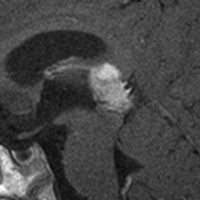

松果体細胞腫の例3(典型例)

これも偶然発見された無症状の女性の小さい松果体細胞腫ですが,ほとんど実質性でのう胞がありません。右はCISSという画像です。中脳の視蓋は圧迫されて変形していますが,中脳水道がまだ閉塞していないのがよくわかります。